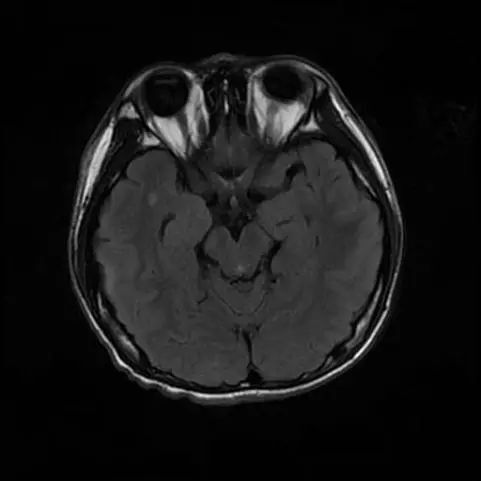

10岁女孩重度结核脑膜炎性脑积水被多家医院告知没有办法治了但经李小